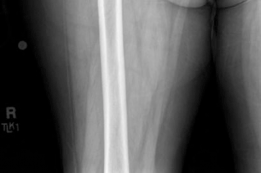

Standard antero-posterior and cross-table lateral radiographs of the pelvis and left hip were obtained immediately following the primary clinical assessment.

The initial AP pelvis radiograph clearly demonstrated a displaced left femoral neck fracture. The fracture line was entirely intracapsular. The femoral head was superiorly and posteriorly displaced relative to the femoral neck, with evidence of approximately 1.5 cm of shortening. The bone quality appeared reasonable for the patient's age, with a preserved Singh index and cortical thickness in the diaphyseal region, though some osteopenia was evident in the proximal trabecular patterns. No signs of pre-existing significant hip osteoarthritis (such as joint space narrowing, subchondral sclerosis, or osteophytosis) in the ipsilateral joint were noted. The contralateral hip appeared unremarkable.

Further radiographic views confirmed the complete displacement and the lack of cortical contact between the proximal and distal fragments. The fracture was classified as a Garden Type IV, indicating complete displacement with a loss of trabecular alignment between the femoral head and the acetabulum, where the head has rotated independently of the neck. Furthermore, it was classified as a Pauwels Type III, meaning the fracture line angle was greater than 70 degrees from the horizontal. This vertical fracture orientation indicates extremely high shear forces across the fracture site, portending a very poor prognosis for osteosynthesis and a high risk of nonunion or fixation failure if internal fixation were to be attempted.